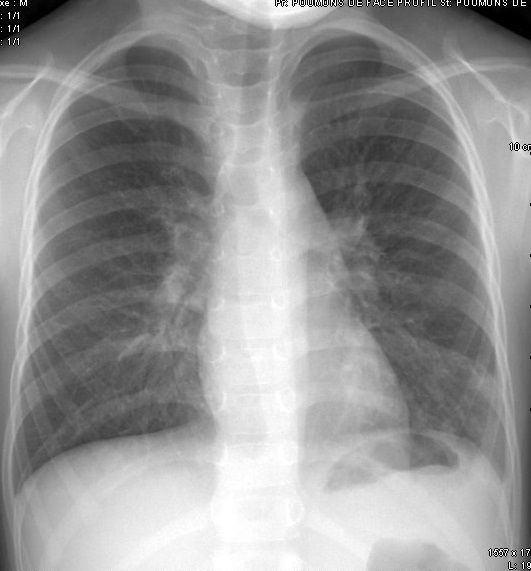

Les radiographies sont fréquemment requises entre autres, pour la recherche d'une fracture dans le cadre d'un traumatisme, les bilans d'arthrose, les bilans statiques, l'étude des poumons au cours d'une radiographie thoracique ...

Il faut savoir qu'une radio des poumons délivre l'équivalent d'1-2 jours d'exposition aux rayons isonisants naturels